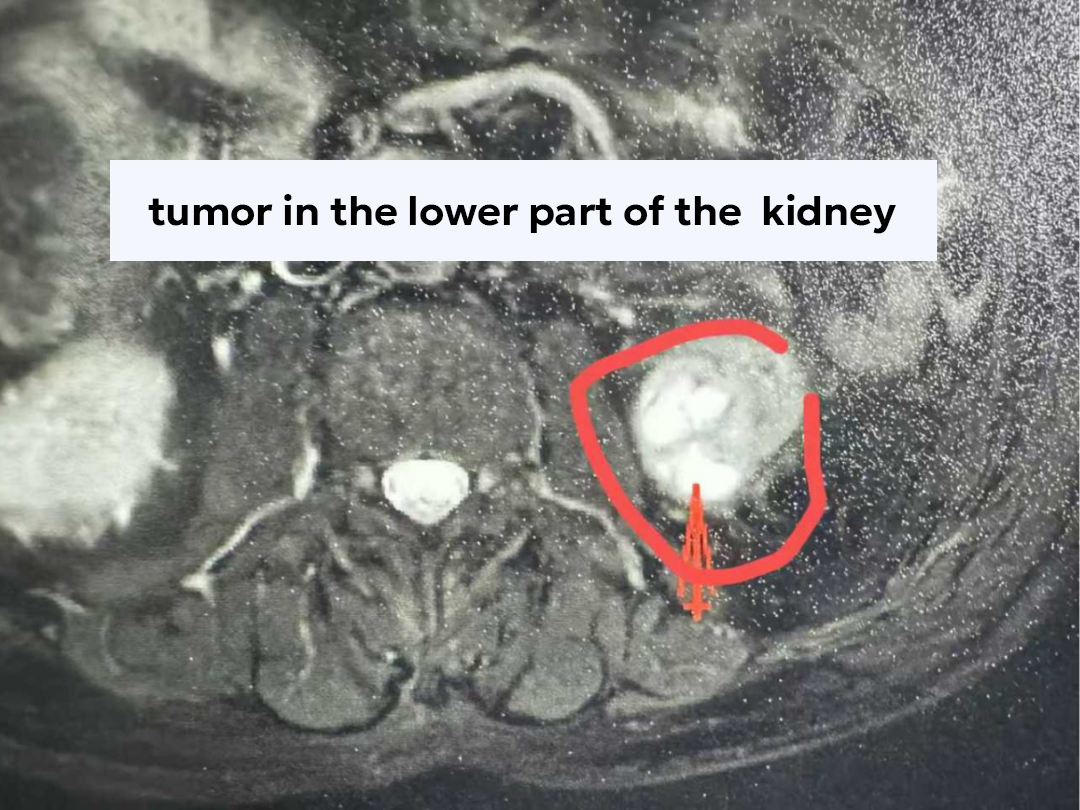

Mr. Li (pseudonym), nearly 80 years old, lives in Inner Mongolia. In September this year, he began experiencing pain in his right kidney and sought medical attention at a local hospital. The examination results raised serious concerns: hydronephrosis of the right kidney, atrophy of the left kidney, and a 3.9 cm mass detected in the left kidney.

This comprehensive evaluation not only confirmed the left kidney tumor as clear cell renal cell carcinoma, but also uncovered a hidden, potentially life-threatening condition, providing a crucial basis for an integrated treatment strategy.

Cryoablation destroys tumor cells by freezing them at ultra-low temperatures. With minimal trauma and rapid recovery, it is especially suitable for elderly patients with multiple comorbidities.